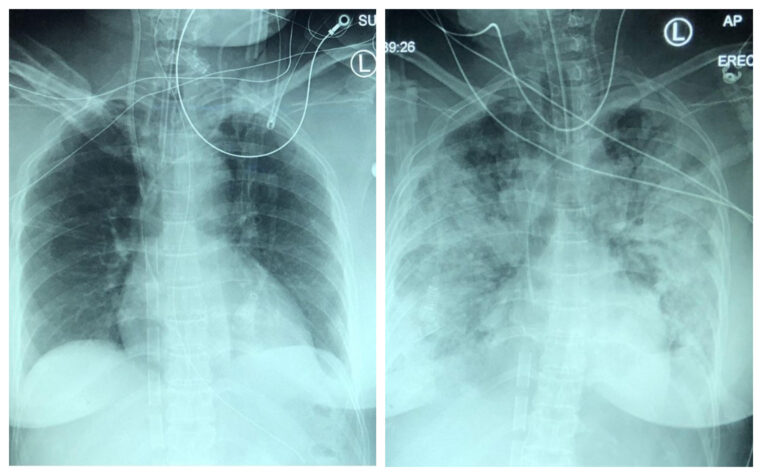

Évolution d’une pneumonie chez une personne touchée par la Covid-19 en 5 jours

galerie-rayon-x-covid